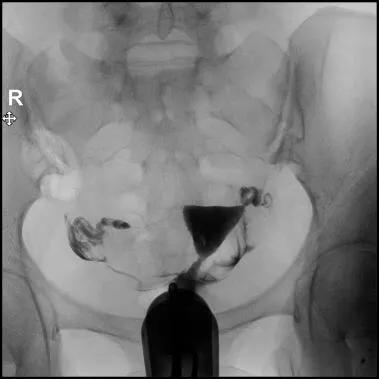

8.透视下注对比剂,动态观察造影剂逐渐膨胀宫腔,流入输卵管,经过伞端流入盆腔的全过程,同时拍摄X光片;

充盈片